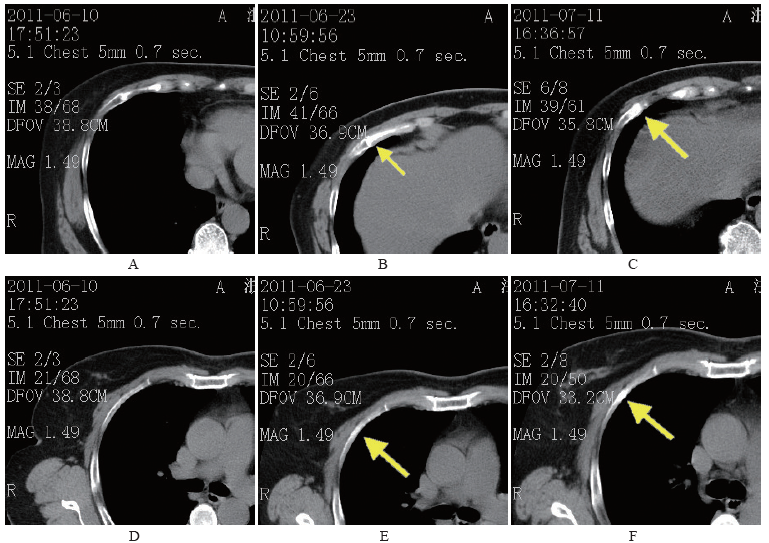

青年女性胸痛近半月 原因竟是

青年女性胸痛近半月 原因竟是